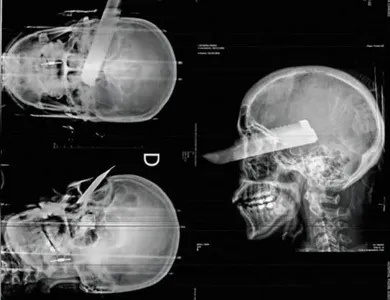

Autor A faca foi cravada no olho direito da mulher - Foto: Polícia Civil

Um homem foi preso em flagrante na última segunda-feira (2) suspeito de tentar matar a companheira em São Carlos, no Oeste de Santa Catarina. Durante o ataque, a vítima foi atingida por um golpe de faca que ficou cravado em seu olho direito. Apesar da gravidade do ferimento, a mulher sobreviveu e conseguiu buscar socorro com vizinhos.